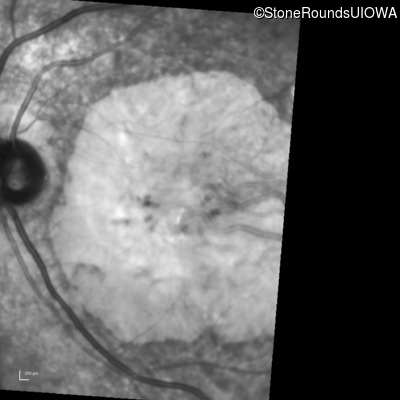

Infrared Fundus Photograph - Right - 20/160 +2 sc

Exemplar